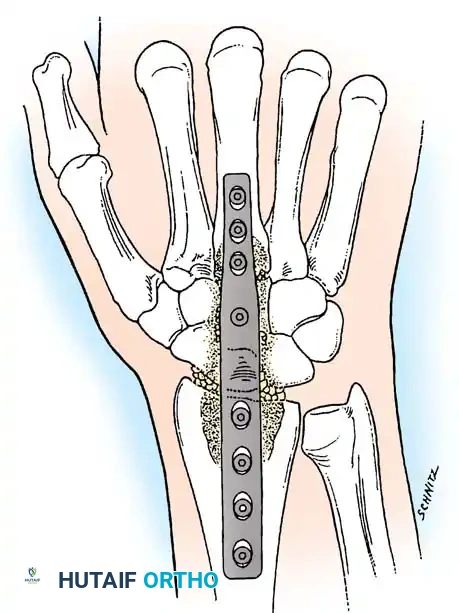

Fig. 4-20: Dorsal view of wrist fusion with AO wrist fusion plate (low-contact dynamic compression plate).

- Distal Fixation: Mark the position of the most distal hole. Remove the plate, drill a 2.0-mm hole in a dorsal-to-volar direction (centered in the metacarpal), tap, and insert a 2.7-mm cortical screw.

- Compression: Fill the remaining metacarpal holes with 2.7-mm screws. Next, apply axial compression across the radiocarpal and intercarpal joints by placing a 3.5-mm screw in the compression mode (eccentric drilling) through the second-most distal hole in the radius.

- Final Fixation and Closure: Fill the remaining radial holes with 3.5-mm screws. Insert the dedicated capitate screw if the plate design allows. Thoroughly irrigate the wound, place a small closed-suction drain, and meticulously close the extensor retinaculum (often leaving the EPL transposed subcutaneously to prevent attrition rupture) and skin.